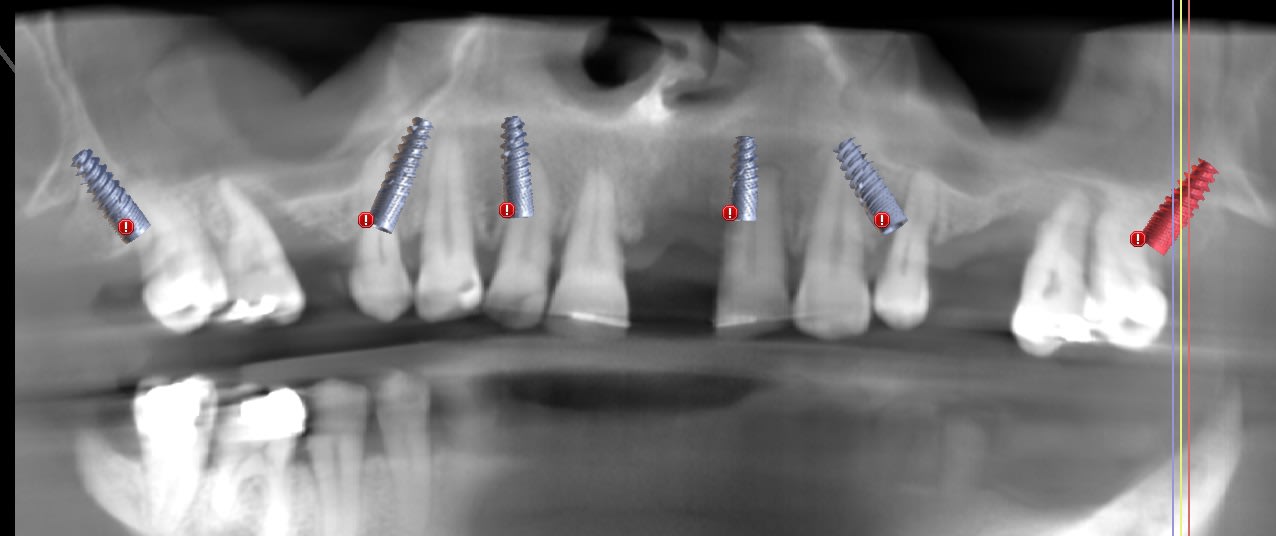

Cas 1 : Implants de 14 et 12 mm, tous en appuis bi-corticale, patiente agé, emergence des implants distaux au niveau des 5. zone assez cicatrisés pour les implants , sauf pour 12 mais qui a un bon ancrage palatin. Pas trop de solution pour en mette 6. rien en distal. Bon cas de AO4 a mon avis.

cas 2 : pareil. un seul implant de 12, 3 en 14 mm. zone edentée tres fine, juste un peu de place la ou j'ai mis l'implant 22. os type 4 en arriere des 7. patiente de 65 ans.

cas 3 : patient 50 ans. avoir des 7 est plus important . implants plus court : 4 de 12, un 14 et un 10. émergence des implant en 14 24 : obligation de chercher un appuis postérieur : deux ptérygoidiens.

Pas de guide à étage : guide appuis osseux, bridge a armature métal avec pilier collé en bouche avec indexation du bridge grâce aux clavettes du guide.